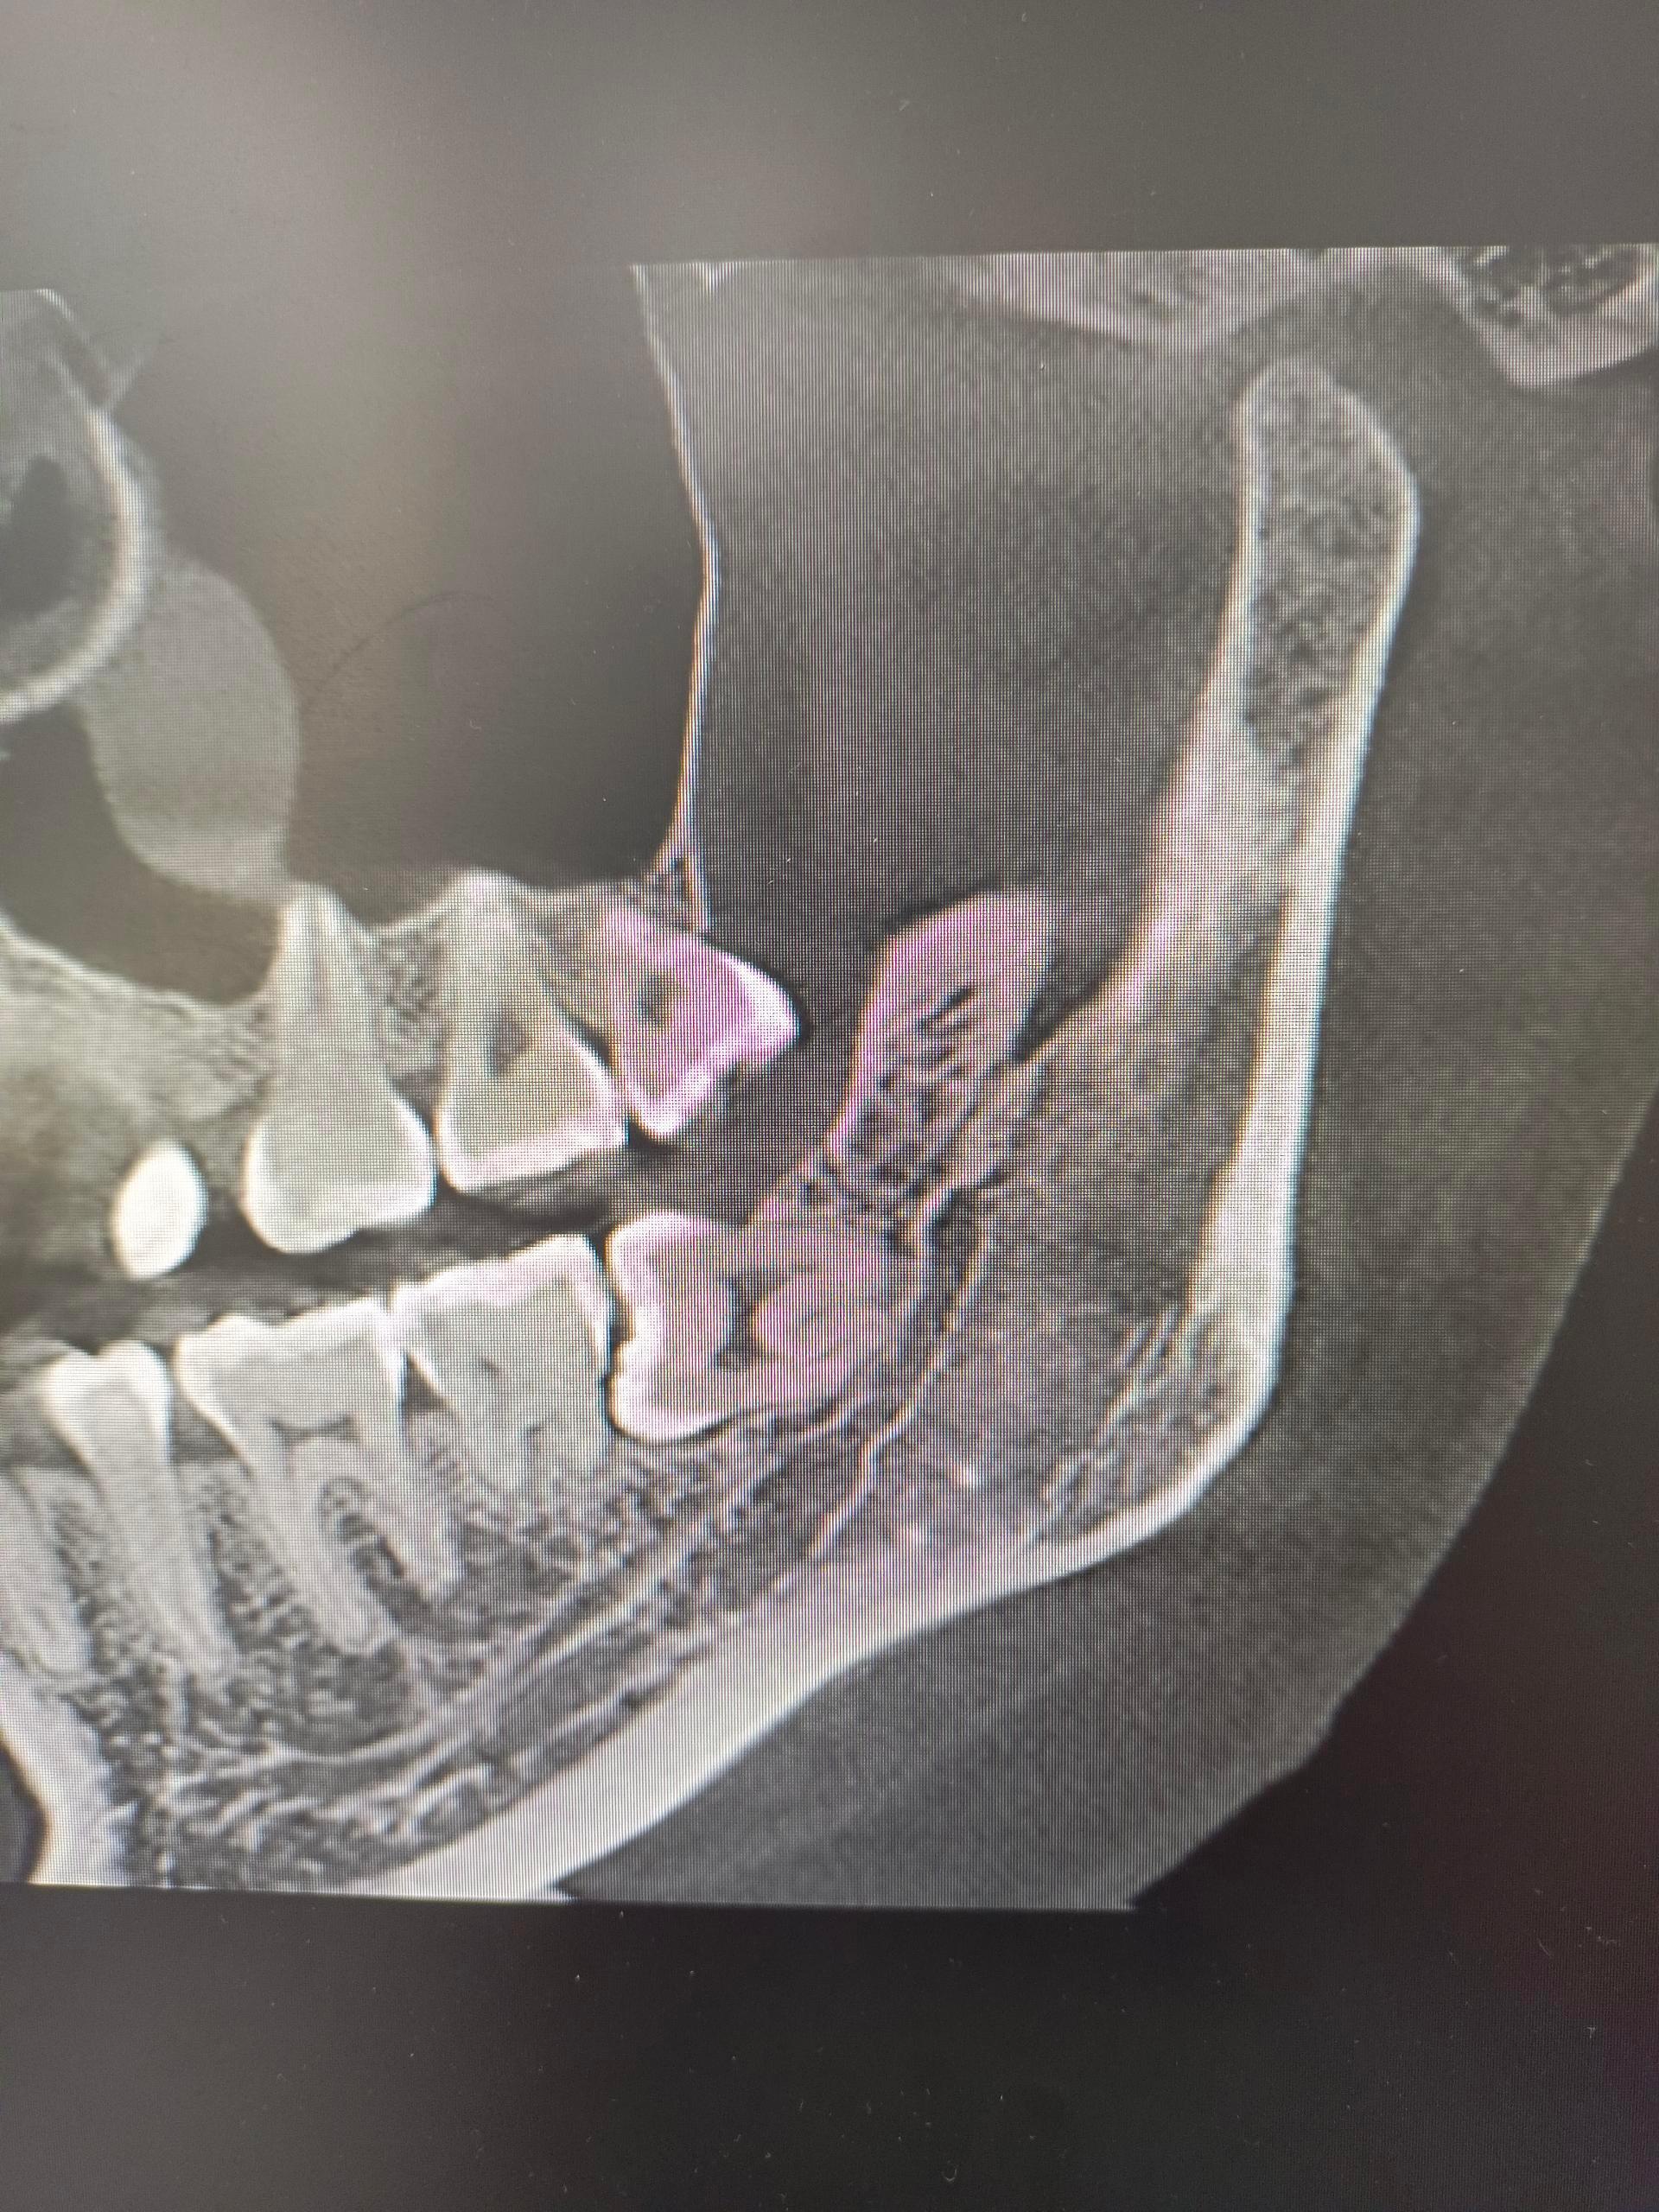

牙科院长来了都不敢拔的牙齿